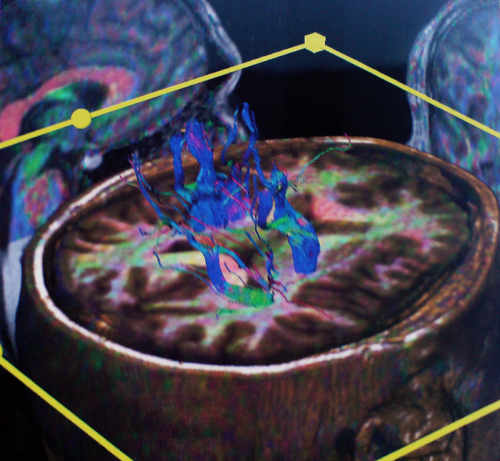

Στο μοντέλο αυτό μπορούν να συνεισαχθούν και πληροφορίες από άλλες ακολουθίες της μαγνητικής τομογραφίας, π.χ. λειτουργικές ακολουθίες όπου απεικονίζονται θέσεις κέντρων του λόγου ή της κίνησης ή ακολουθίες δεσμιδογραφίας όπου απεικονίζονται νευρικές οδοί στο βάθος του εγκεφάλου. Ο χειρουργός έχει έτσι την δυνατότητα να σχεδιάσει προεγχειρητικά την επέμβαση, αποφεύγοντας για παράδειγμα προσπελάσεις που αυξάνουν τον κίνδυνο τραυματισμού ευγενών περιοχών του εγκεφάλου ή μεγάλων αγγείων. Η ταύτιση του ψηφιακού μοντέλου με τον προεγχειρητικό σχεδιασμό και της πραγματικής ανατομίας γίνεται στο χειρουργείο με την |

Δεσμιδογραφία (DT MRI) εγκεφάλου |